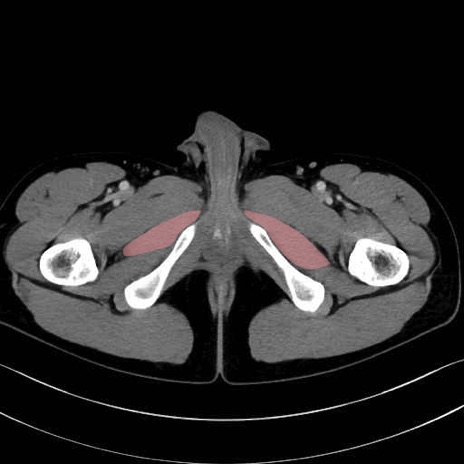

大内転筋(Adductor magnus)、小内転筋(Adductor minimus) のCT画像の解剖

6. 大腿内側(内転筋群)

大内転筋・小内転筋 (Adductor magnus / Adductor minimus)